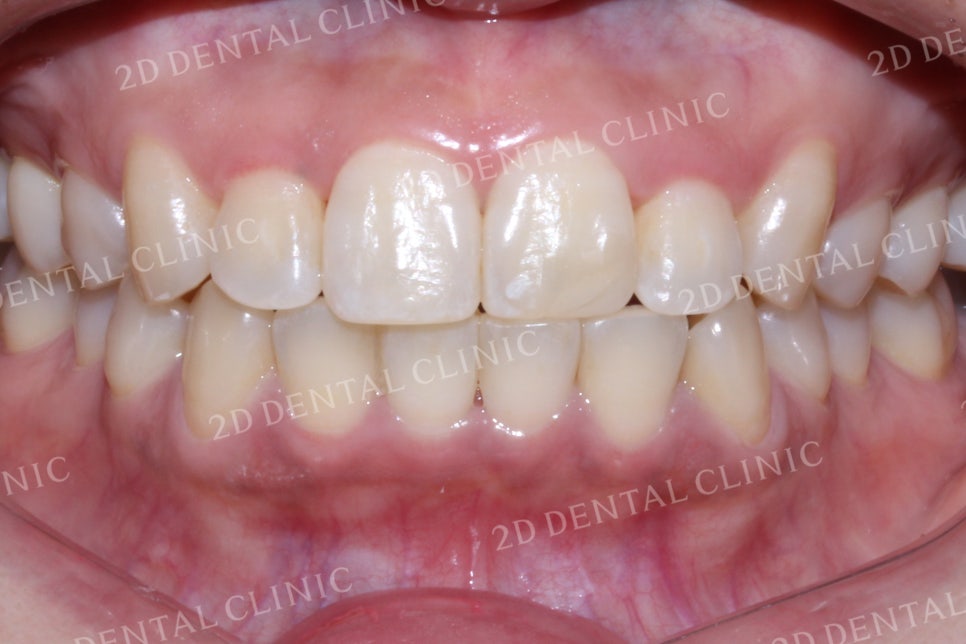

전치부 치아의 교합 역시

측절치가 반대로 물리던 교정 전과 달리

교정 후 바른 교합 상태로 교정되었습니다.

또한 들쭉날쭉했었던

하악의 전치부 치아들도

가지런한 모습으로 바뀌었습니다.